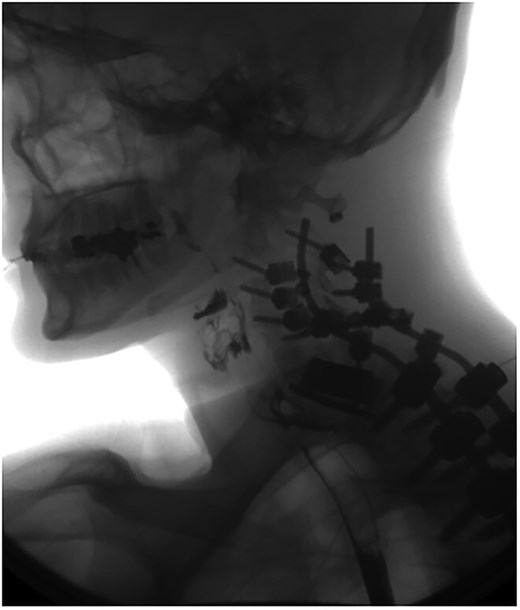

A 35-year-old male presented with a month-long history of dysphagia, severe headache, and posterior neck pain that radiated to the occiput. His medical history was significant for cervical surgeries, including an anterior cervical discectomy and fusion (ACDF) at C5/C6 one year and two months ago (Fig. 1). Shortly thereafter, the patient underwent revision surgery along with posterior plating from C5 to T1 due to osteomyelitis, worsening cervical deformity, and retropharyngeal abscess (Fig. 2). Initial workup included a noncontract computed tomography (CT), demonstrating increased gas density at C6 corpectomy site and post cricoid region (Fig. 3). A swallow study was obtained based on suspicion of a perforation and demonstrated extraluminal leakage of contrast posteriorly at the C6 level, consistent with initial CT (Fig. 4). Surgery included removal of the anterior and posterior hardware and esophageal repair. Although initially the esophageal injury was suspected to be related to the hardware, intraoperatively, it was found the instrumentation was not in communication with the esophagus. This confirmed the perforation was unrelated to direct injury from the cervical hardware construct, which was intact. The esophagus was repaired with a pectoralis flap. The postoperative course was uneventful, and the patient was discharged home after one week. The patient later died due to severe complications of substance abuse unrelated to the operation.

Sagittal CT of initial ACDF at cervical spine C5/C6 level over one year prior to esophageal perforation.